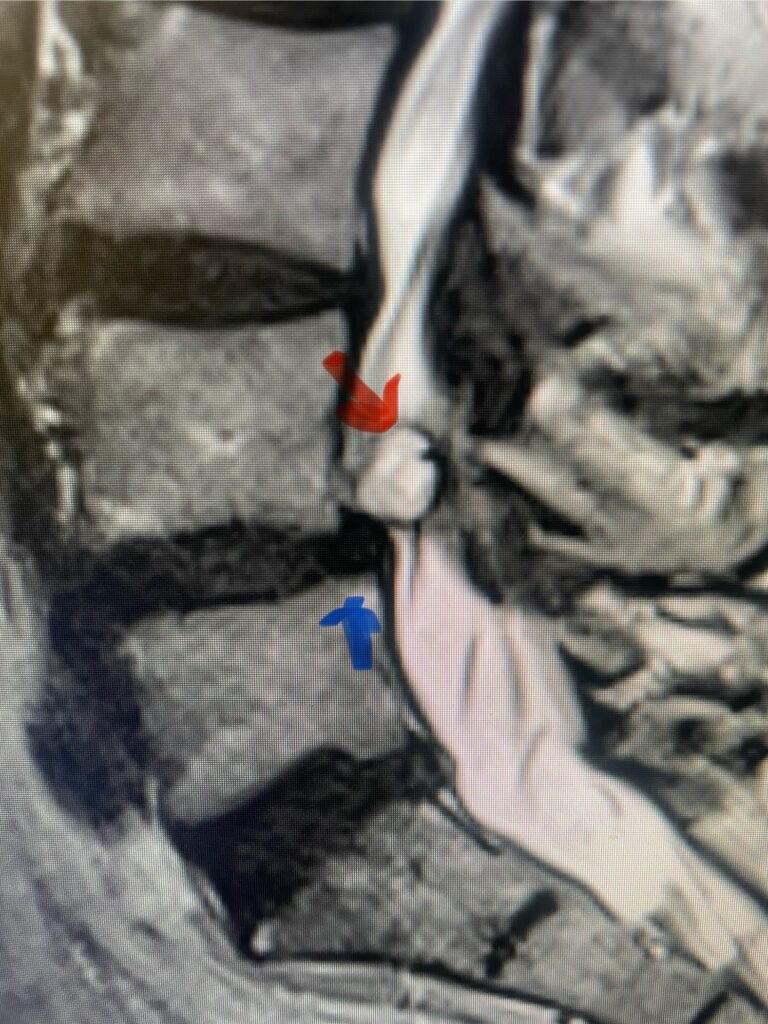

The spinal synovial cyst is one of the most interesting expressions of spinal instability. They emanate from the synovial lining of a degenerated facet joint that […]